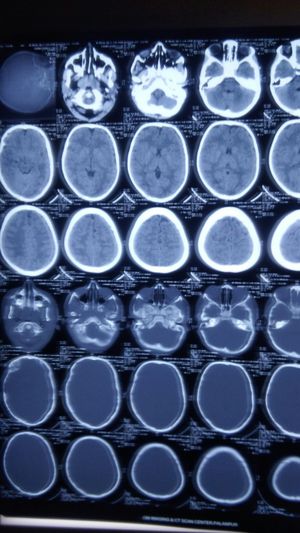

A 7 years old girl Alleged RTA Admit Emergency room under Neurosurgeon... And complain H/O Local vomiting, Nasal bleed present, ?convulsions and Examination.. unconscious, GCS E2V2M2,  pupils BERL, Lt side chest crepitation present, Lt side chest and neck surgical Emphysema noted, P 190/min,RR 60/min,Spo286%With o2,  Abrassions over forehead present.....A CT head performed what is that most likely diagnosis

Subdural haemorrhage, cresent like hypodense lesion seen at the left side of cerebrum.

Lt sied SDH peri tempral regan.and ethmoed fracture. Survive chance are very poor